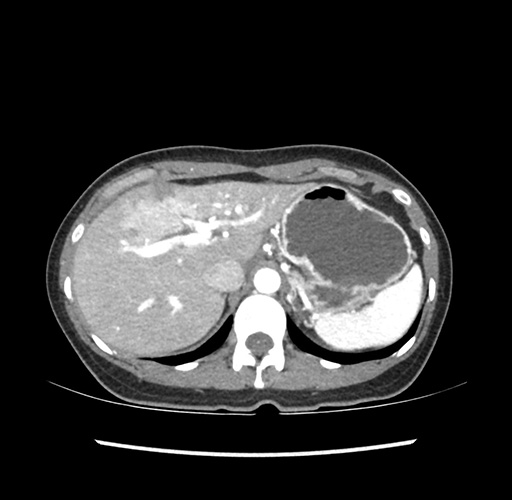

Left lateral sectionectomy [case 12]

Imaging Analysis

Look through the patient's CT scan to identify any areas of concern for the necessary procedure.

Based on your CT findings, which issue(s) would give reason for "planned slowing down moment(s)" in this case?

Considering a standard left lateral sectionectomy procedure, what step(s) of the operation would you do differently in this case ?